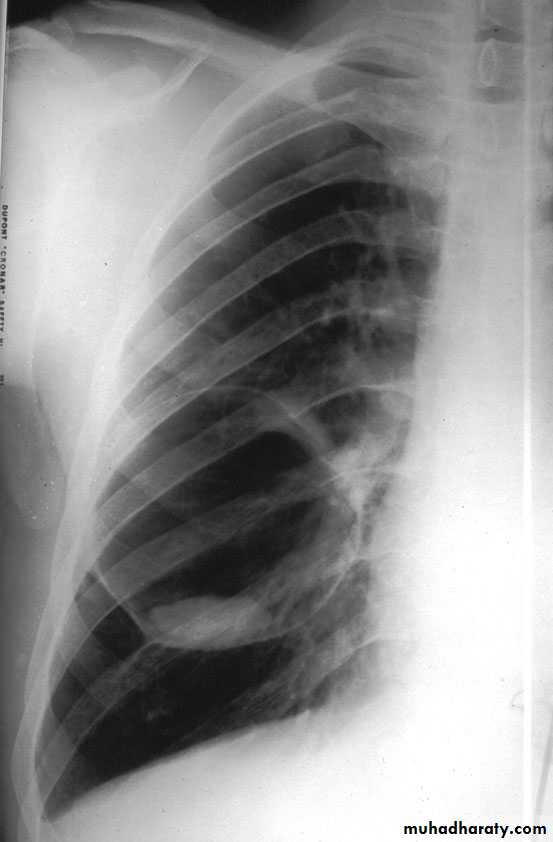

Bronchopneumonia